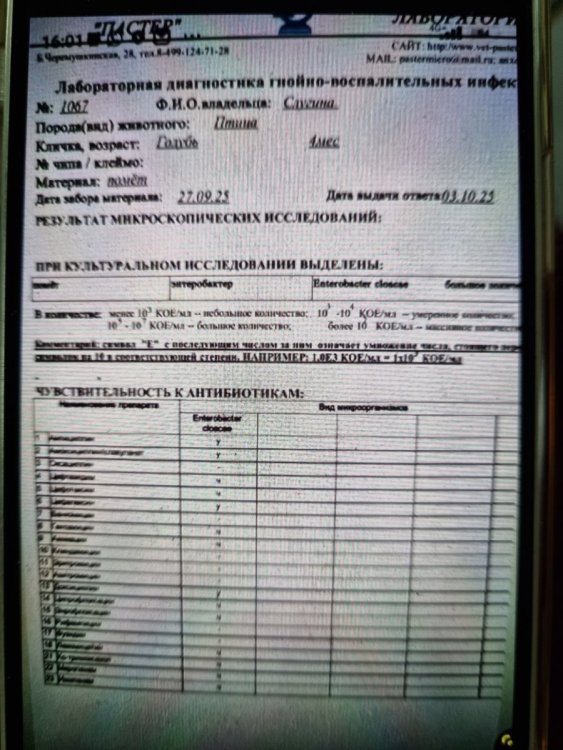

Это не у меня только так, вот люди в соседней теме сдавали параллельно в двух лабораториях, в одной лаборатории есть чувствительность к доксициклину, в другой нет